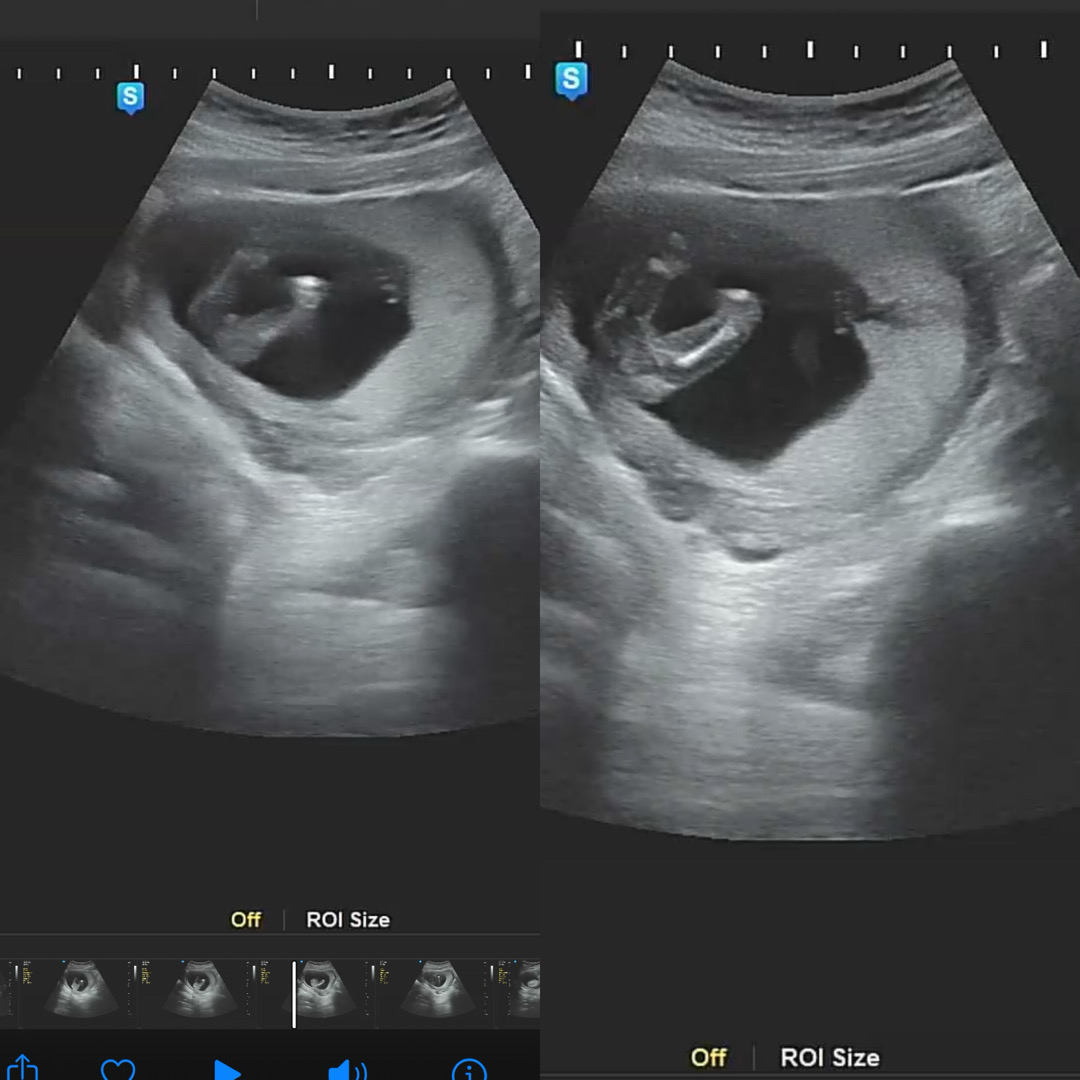

다리사이 성별.. 봐주세여ㅠㅠㅠ

딸인거같이 매끈한거같은데 또 보면 아들같아서 다들 어떻게 생각하시나용 ㅠㅠㅠ 딸인지 아들인지… 봐주세여ㅠ

저는 여자같아요 튀어나온게 없어요

아들같아요